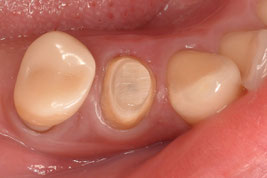

2日目にファイバーコアを植立しました。

軸面の健全歯質を大幅に残したうえで、オーバーレイの形態で修復しました。インジェクションモールディング法を応用しております。直接修復なので、海外からの来院であっても、短期滞在で対応可能です。

ダイレクト修復に完全移行してから、歯冠形成が大きく変わりました。アンダーカットを積極的に付与するようになり、形成のキレイさを気にせず、健全歯を最大限残す形態になりました。

インジェクションモールディング法を用いて、ダイレクトクラウンにて完了させました。ファイバーコアによる支台築造と同時にダイレクトクラウンを成形するため、歯根・築造体・クラウンとが一体化したモノブロック構造で強度を担保できます。ファイバーコアからダイレクトクラウンまで一気に進めて、だいたい2時間の施術時間です。施術中にドクターが離れることができないのですが、圧倒的な時間短縮です。